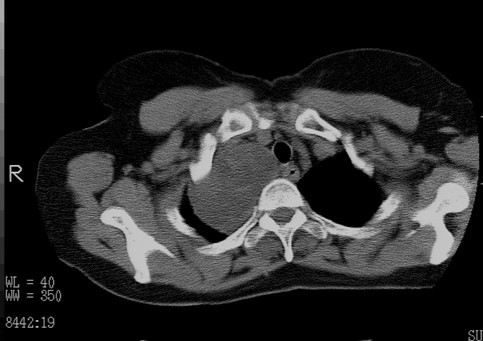

以下是引用随光逐影在2010-3-1 8:36:00的发言:[br]右上纵隔囊性占位性病变,考虑支气管囊肿,不排除神经源性肿瘤。